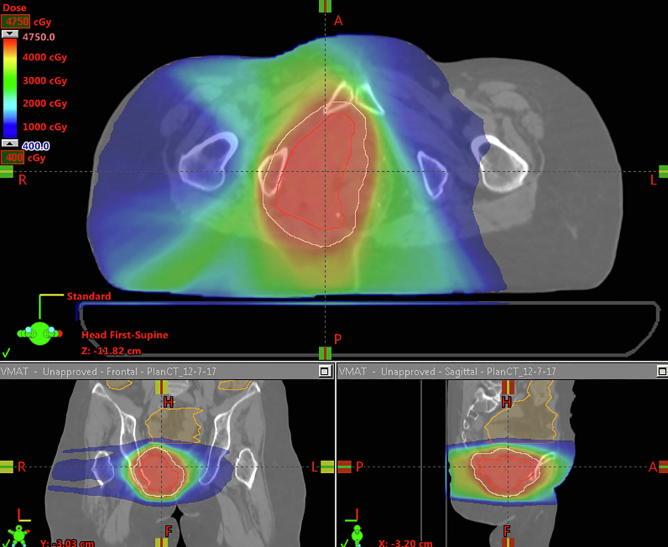

All patients who received hyperfractionated, accelerated PBR re-RT to the pelvis from 2007 to 2017 were identified. Re-RT was delivered twice daily with a 6 h minimum interfraction interval at 1.5 Gray Relative Biological Effectiveness (Gy(RBE)) per fraction to a total dose of 39-45 Gy(RBE). Concurrent chemotherapy was given to all patients. Comparison photon plans were generated for dosimetric analysis. Dosimetric parameters compared using a matched-pair analysis and the Wilcoxon signed-rank test. Survival analysis was performed Kaplan Meier curves.

Fifteen patients were identified, with a median prior pelvic RT dose of 50.4 Gy (range 25-80 Gy). Median time between the initial RT and PBRT re-RT was 4.7 years (range 1.0-36.1 years). In comparison to corresponding photon re-RT plans, PBR re-RT plans had lower mean PBM dose, and lower volume of PBM getting 5 Gy, 10 Gy, 20 Gy, and 30 Gy (p < 0.001, p < 0.001, p < 0.001, and p = 0.033, respectively).With median 13.9 months follow-up after PBR re-RT, five patients had developed local recurrences, and four patients had developed distant metastases. One-year overall survival following PBR re-RT was 67.5% and one-year progression free survival was 58.7%. No patients developed acute or late Grade 4 toxicity.